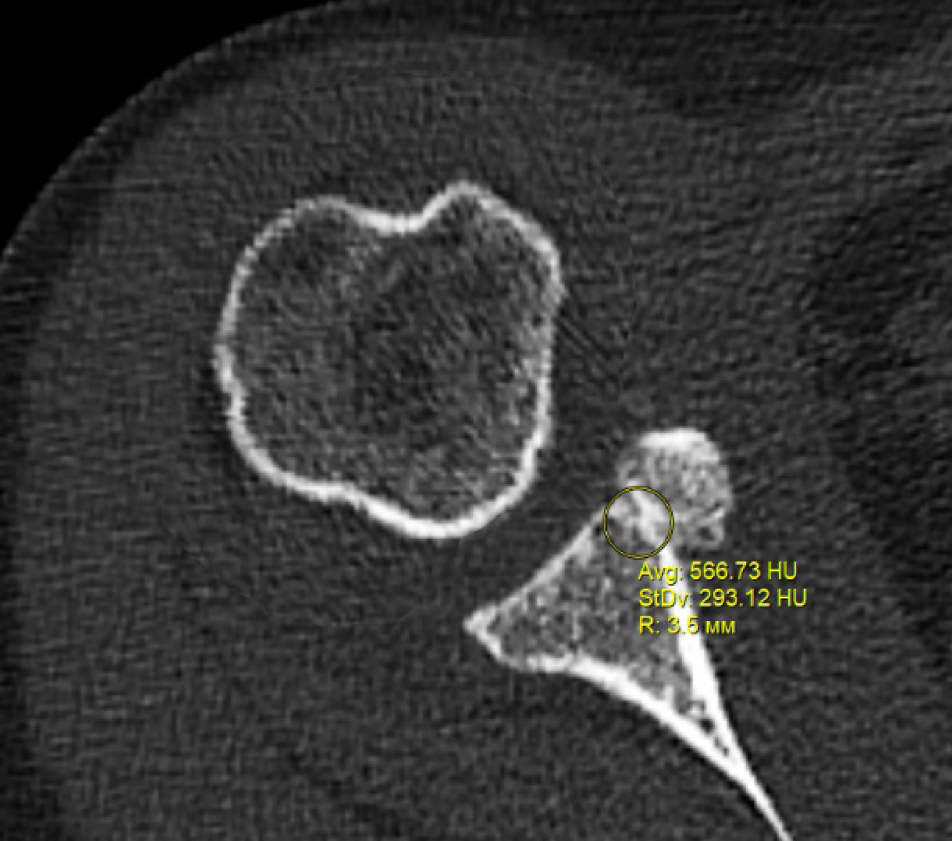

В программном обеспечении, на аксиальных КТ срезах оперированного плечевого сустава, выбирали инструмент «круг», который позволял посчитать среднюю плотность тканей внутри круга в единицах Хаунсфильда. Шкала единиц Хаунс-филда (HU) – шкалалинейного ослабления излучения по отношению к дистиллированной воде, рентгеновская плотность которой была принята за 0 HU (при стандартных давлении и температуре). Круг устанавливали таким образом, чтобы одна его половина была заполнена тканью гленоида, вторая половина тканью трансплантата (рис. 1–3). Оценивали плотность тканей над проксимальным винтом, между винтами, под дистальным винтом. Полученные данные анализировали с помощью пакета Microsoft Excel.

Рис. 1. Оценка плотности ткани под дистальным винтом

Через 3 месяца после оперативного лечения по данным анализа КТ срезов были получены следующие результаты: плотность ткани над проксимальным винтом составили (424 ± 24,3) HU, между винтами (460 ± 23,4) HU, под дистальным винтом (587 ± 49,1) HU. Спустя 6 месяцев после операции плотность ткани над проксимальным винтом составили (320 ± 28,7) HU, между винтами (424 ± 36,2) HU, под дистальным винтом (623 ± 33,4) HU. Через 12 месяцев после операции показатели были следующие над проксимальным винтом (276 ± 22,1) HU, между винтами (387 ± 31,1) HU, под дистальным винтом (662 ± 43,2) HU (таблица).